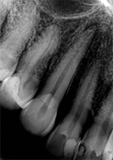

antes depois